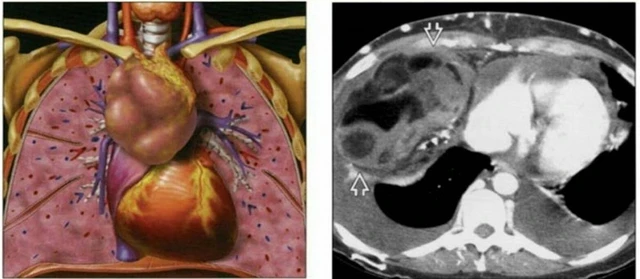

U trung thất có thể lành tính hoặc là khối u ác tính. Hiện nay chưa có biện pháp nào để phòng ngừa bệnh u trung thất. Tuy nhiên, bạn có thể cải thiện cơ hội điều trị bằng cách khám sức khỏe tổng quát định kỳ, phát hiện sớm khối u nếu có. Nếu bạn bị khó thở, ho hoặc các triệu chứng khác kéo dài hơn hai tuần, hãy đến gặp bác sĩ để được thăm khám và điều trị sớm, tránh nguy cơ tăng nặng của bệnh.